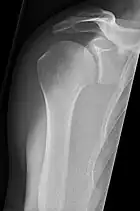

• Humerus - AP and Lateral